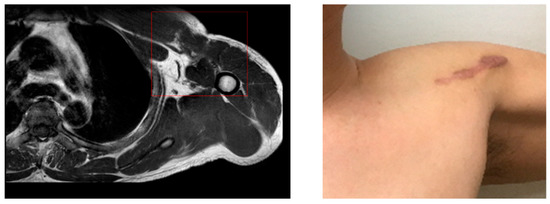

After a magnetic resonance imaging (MRI) at a local hospital, it was advised that the patient be moved to a superior hospital for surgery (Figure 1).

Seven days later, the MRI was read by a radiologist; the final diagnosis was a complete rupture of the pectoralis major muscle. In a physical examination conducted by an orthopedic surgeon, active forward flexion ROM was almost 160 degrees; however, external rotation was passively possible to 30 degrees, and internal rotation was limited at 35 degrees. The patient complained of pain and considerable discomfort during the examination.

Figure 1. Patient’s MRI and injury site.